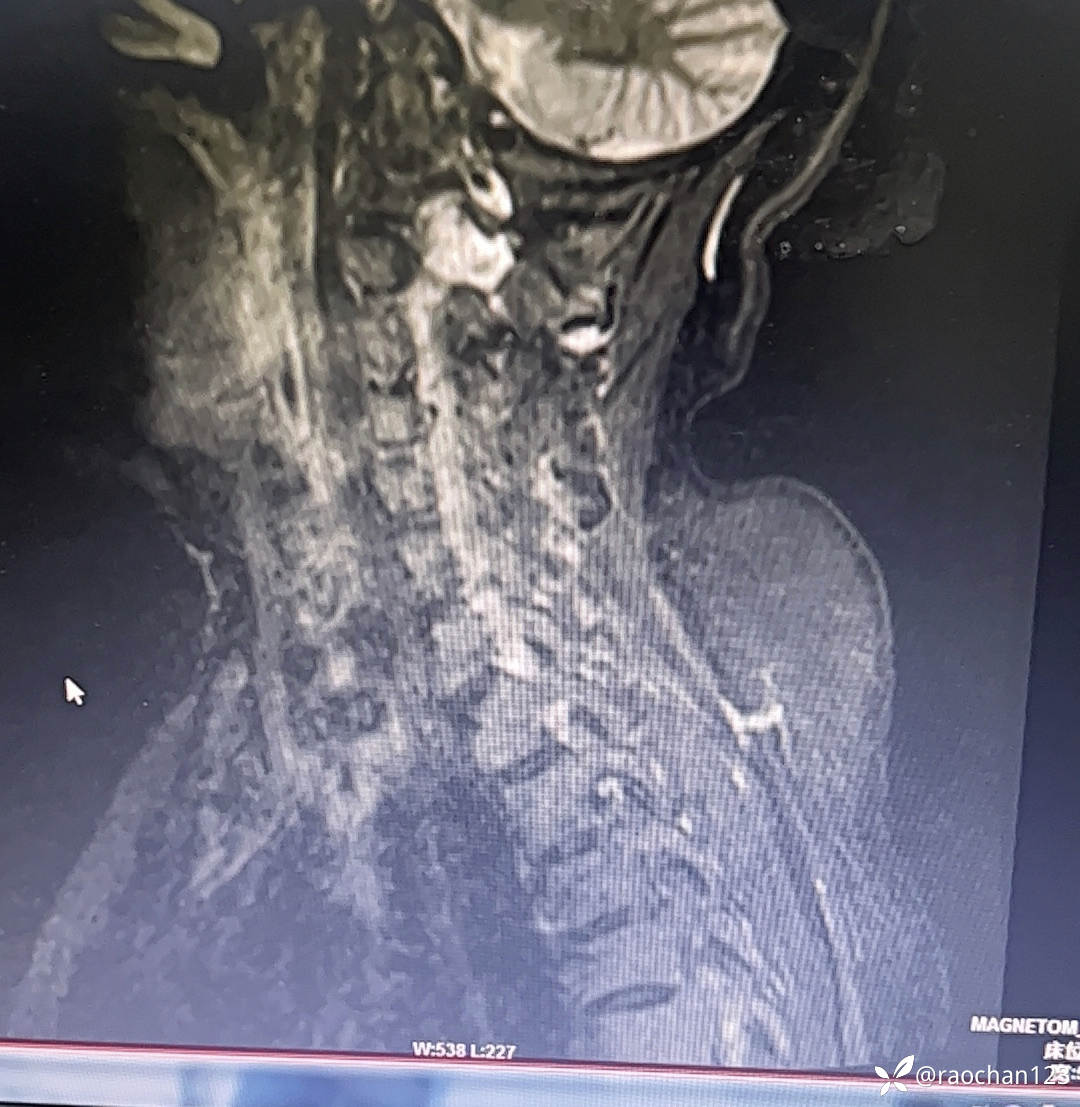

【治疗经过及结果】:给予低流量吸氧,布洛芬混悬液 解热 镇痛,左氧佛沙星抗炎(既往有头孢过敏史)、止痛,热毒宁注射液 清热解毒;艾箱灸、中药塌渍、中药涂擦、火罐、TDP、中药热奄包等中医外治通络祛痛等治疗后,仍有发热,肌酸、肌痛、关节疼痛症状。复查血常规:2024-11-8 13.93# 谷丙转氨酶 45U/L 天门冬氨酸 25U/L 白蛋白 27.0g/L 进一步查乳酸脱氢酶 284U/L 肌酸激酶 26U/L,PCT 0.44ng/ml BNP 811ng/L 免疫五项中IgGA 5.38g/L 血钙 1.94mmol/L 尿微量白蛋白 32.2mg/L 25羟基维生素D 22.68ng/ml 甲胎蛋白、癌胚抗原(-)。颈椎MRI:1.颈椎骨质增生,C4/5、C5/6、C6*7椎间盘轻度突出2、颈后皮下软组织内脂肪堆积,请结合临床。(后颈部皮下软组织内可见异常信号影,T1T2呈高信号,压脂序列呈低信号,颈椎生理曲度变直,椎体后缘连线尚连续,椎体缘骨质光滑,各椎间隙未见狭窄,椎体信号欠均匀,部分椎间盘T2信号减低,C4/5、C5/6、C6/7椎间盘向后轻度突出,硬膜囊轻度受压,椎管无狭窄,黄韧带无肥厚,颈隋未见明显异常)。骨密度:骨质疏松(T值 -4.2)。抗ANA抗体 RF 抗CCP抗体 ENA抗体谱结果待回。患者服用布洛芬混悬液后出现大汗淋漓,血钙偏低,调整为停服布洛芬混悬液、给予醋酸泼尼松10mg 2次/日 口服 解热、抗炎、止痛,金钙尔奇 600mg 2次/日,骨化三醇 0.25ug/日 口服 改善骨质量,暂给予肠内蛋白营养(患者饮食无异常),余治疗同前。